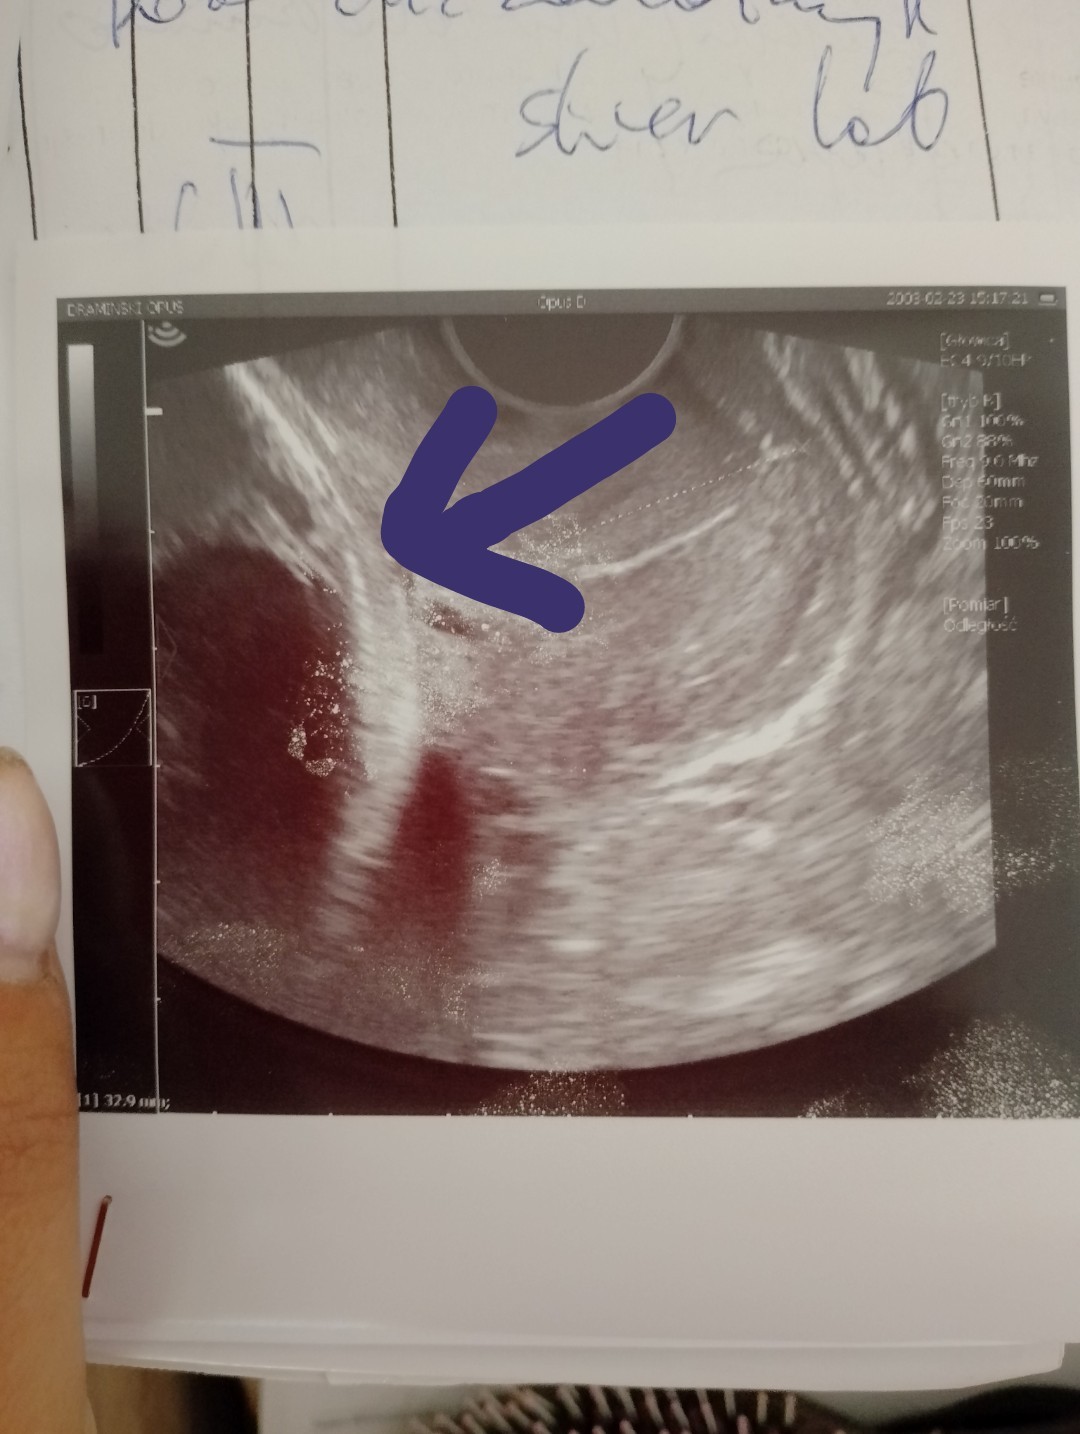

Ktoś mi może co to może być ? Czy to główka czy worek owodniowy? Lekarz mówił że wszystko w porządku ale zastanawia mnie co to jest

Załączniki

• IMG_20240706_094514_1.jpg

IMG_20240706_094514_1.jpg

201,4 KB · Wyświetleń: 129